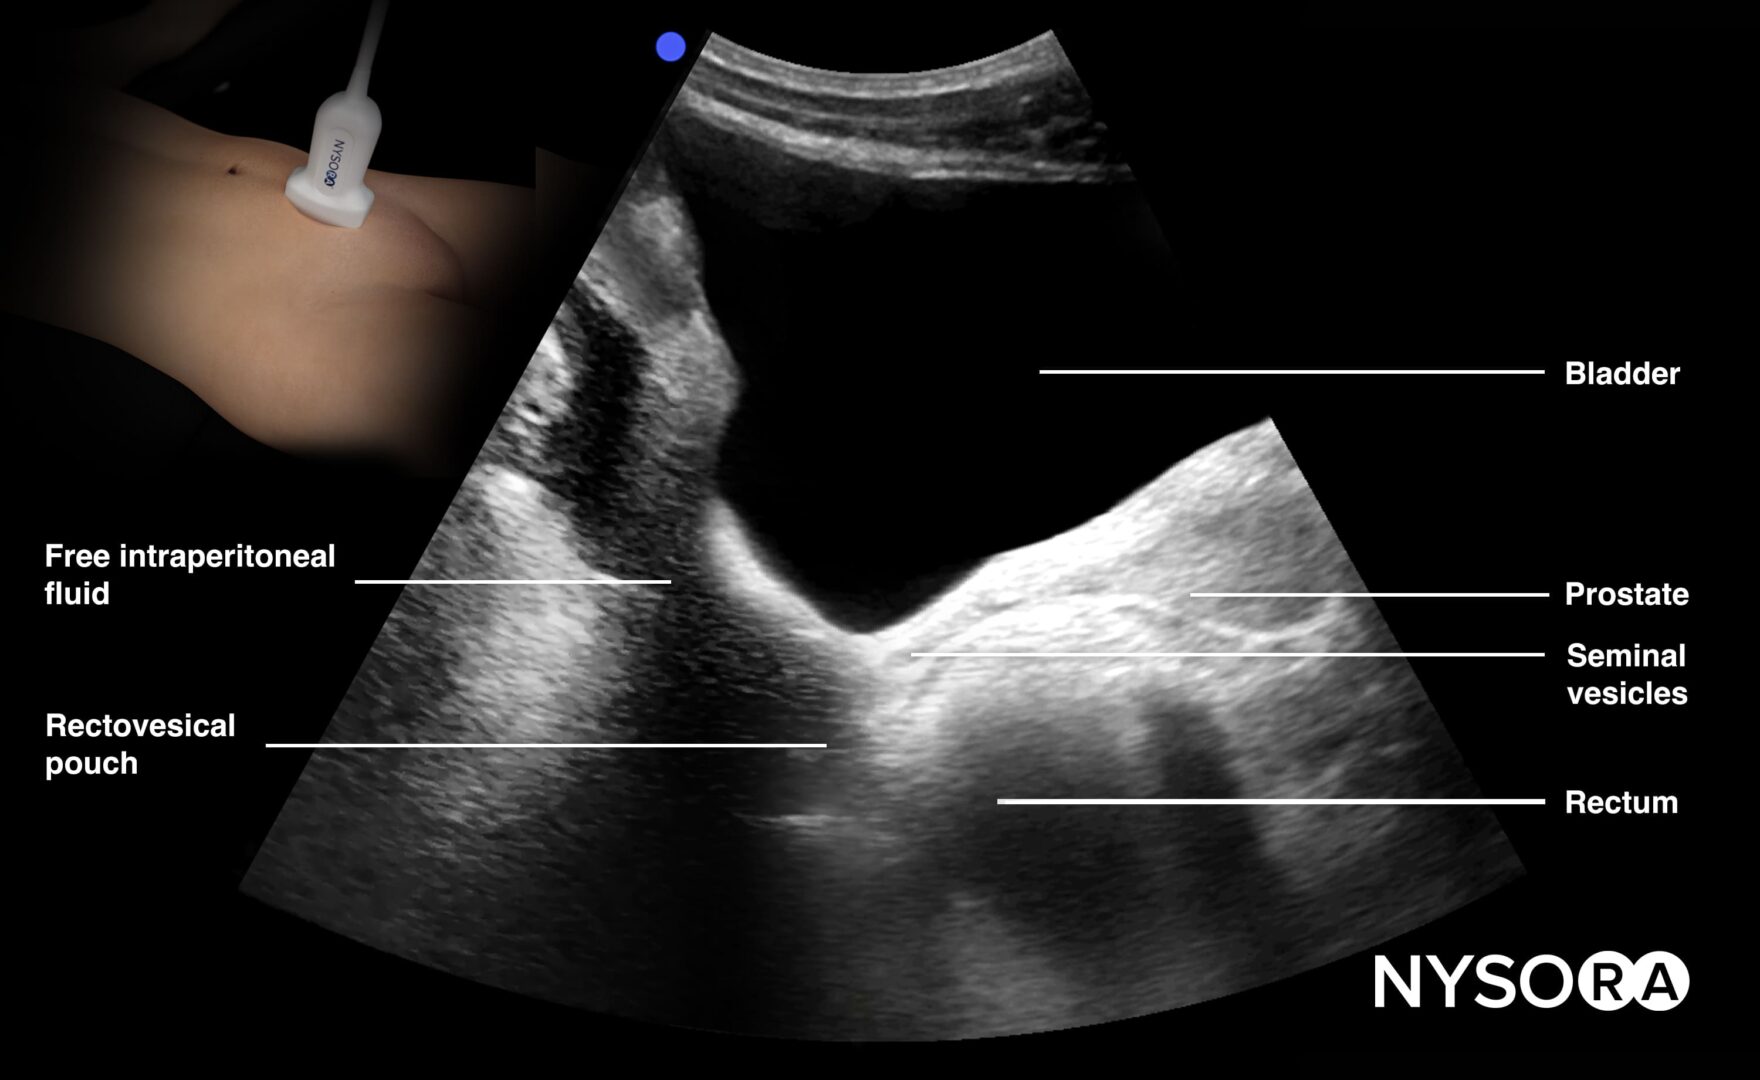

A comprehensive learning tool for anesthesiologists, emergency, and critical care physicians, offering structured modules across eight organ systems, including lung, cardiac, abdominal, renal, and vascular. It integrates step-by-step protocols with high-quality ultrasound images, videos, animations, and NYSORA’s Reverse Ultrasound Anatomy to simplify interpretation of normal and pathological findings.

Detailed anatomical illustrations and ultrasound images.

Reverse Ultrasound Anatomy illustrations for intuitive sonoanatomy recognition.

NYSORA’s proprietary Reverse Ultrasound Anatomy simplifies the understanding of sonoanatomy.

Gastric content assessment, vascular access, free intraperitoneal fluid, and more crucial bedside assessments.

Reverse Ultrasound Anatomy illustrations make sonoanatomy easier to understand and apply.

• Abdominal ultrasound (eFAST, gastric content, bowel assessment)